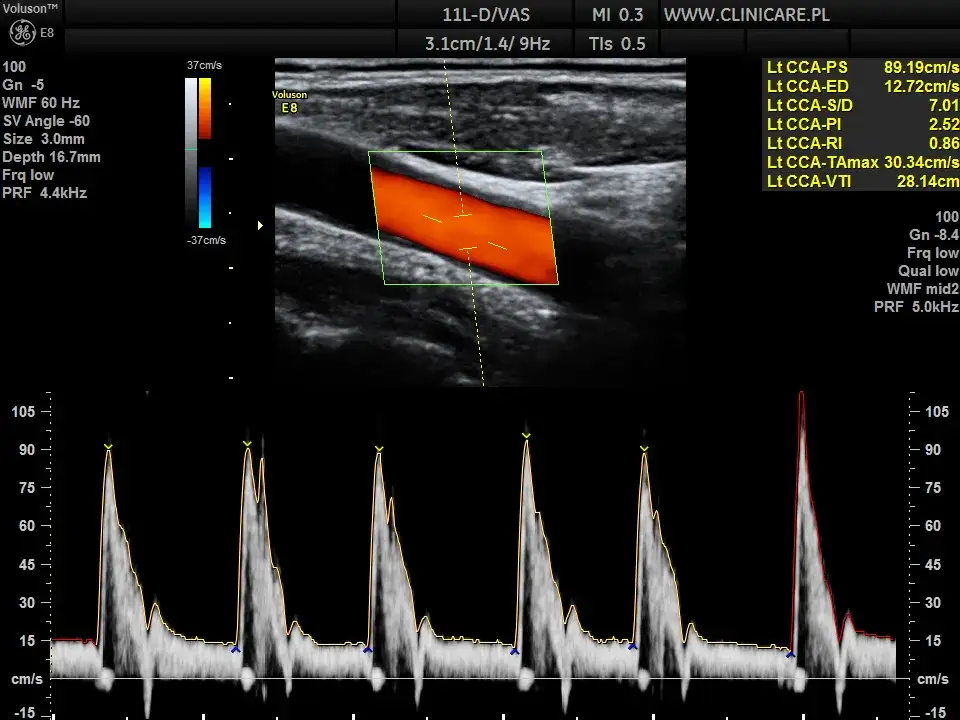

- USG Doppler tętnic szyjnych: To nieinwazyjne badanie pozwala ocenić przepływ krwi w tętnicach szyjnych oraz wykryć obecność blaszek miażdżycowych i stopień zwężenia naczyń. Jest to kluczowe badanie w diagnostyce miażdżycy mózgu.